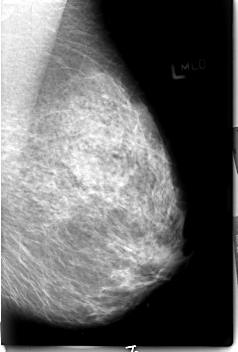

B_3009_1.LEFT_MLO

LEFT_MLO LINES 4568 PIXELS_PER_LINE 3088 BITS_PER_PIXEL 12 RESOLUTION 50 NON_OVERLAY